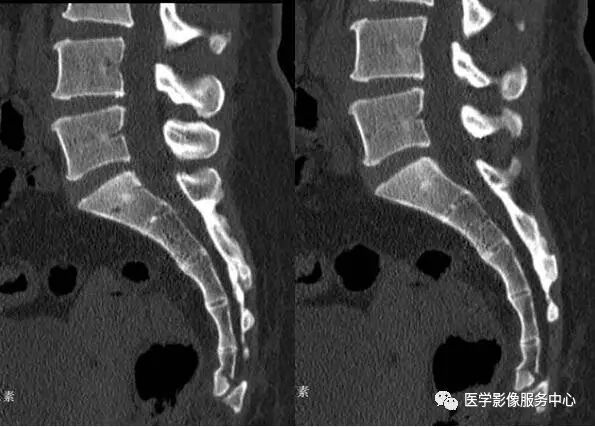

骶骨由5块骶骨融合成一块形成,尾骨由3-5组成。在人类的退化结构中骶尾骨变异较大,特别是侧位的弯曲形态变异较大。研究表明在X线侧位片上骶尾骨共同向前弯曲,但由于其变异较大,弯曲形态各异。

按不同的弯曲形态将其分为:均匀弯曲型、骶骨成角型、尾骨成角型、尾骨脱位型4种类型(见图1-9),其中骶骨成角一般在S3、S4-5和S5部位,成角最大为70°。尾骨成角常在尾1-2或尾2-3部位,成角最大可达80°。

图1:均匀弯曲型;图2:骶骨成角型(骶3);图3:骶骨成角型(骶4-5);图4:骶骨成角型(骶5);图5:尾骨成角型(尾1);图6:尾骨成角型(尾1-2);图7:尾骨成角型(尾2-3);图8:尾骨脱位型;图9:尾骨脱位型

1、骶骨下部成角,并可见前缘骨皮质凹陷,但无骨折透亮线。也就是文中所提到的骶骨成角型变异(见图2-4);

2、尾骨成角,向前 倾斜,关节间隙尚好,无骨折片,易误认为尾骨脱位(见图5-7);

3、尾骨向后滑移,也就文中所说的尾骨脱位型,常易误诊为尾骨脱位(见图8、9)。